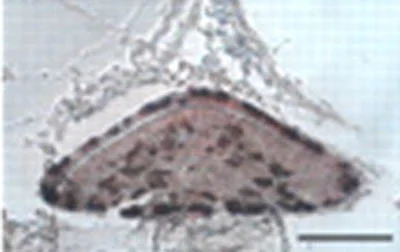

ab74976 staining ACTH in P0 Pitx2-Cre/Dicer1 mutant mice pituitary tissue by Immunohistochemistry (Formalin/PFA-fixed paraffin-embedded sections).

Samples were fixed in 4% paraformaldehyde, dehydrated, and embedded in paraffin wax. Sections were cut (7 μm) and stained with H&E. Immunohistochemistry was performed on 7-μm paraffin sections stained by an indirect immunoperoxidase method. Peroxidase activity was visualized with AEC stain kit. ab74976 diluted 1/200. Secondary antibodies conjugated with biotin were used at 1/150 dilution.

Image from Zhang Z et al, J Biol Chem. 2010 Nov 5;285(45):34718-28. Epub 2010 Aug 31, Fig 4. DOI 10.1074/jbc.M110.126441